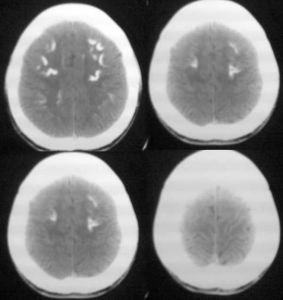

X線頭顱攝片多數可見基底神經節鈣化,骨質較密,小腦出現鈣化點。